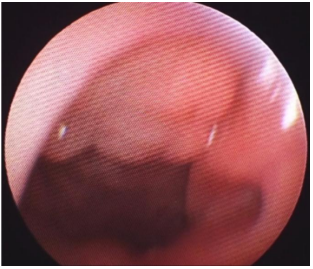

Menina, 9 anos de idade, apresenta febre há dois dias, com picos de até 38,2 °C ocorrendo duas a três vezes ao dia, associada à prostração. Nega coriza, tosse ou rouquidão. Ao exame físico, observa-se linfonodo submandibular direito aumentado, medindo cerca de 2 cm e doloroso à palpação. À oroscopia, observam-se os seguintes achados:

Enunciado 4540961-1

Com base nessas informações, o agente etiológico mais provável nessa situação é: